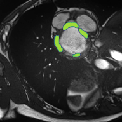

Despite their outstanding accuracy, semi-supervised segmentation methods based on deep neural networks can still yield predictions that are considered anatomically impossible by clinicians, for instance, containing holes or disconnected regions. To solve this problem, we present a Context-aware Virtual Adversarial Training (CaVAT) method for generating anatomically plausible segmentation. Unlike approaches focusing solely on accuracy, our method also considers complex topological constraints like connectivity which cannot be easily modeled in a differentiable loss function. We use adversarial training to generate examples violating the constraints, so the network can learn to avoid making such incorrect predictions on new examples, and employ the Reinforce algorithm to handle non-differentiable segmentation constraints. The proposed method offers a generic and efficient way to add any constraint on top of any segmentation network. Experiments on two clinically-relevant datasets show our method to produce segmentations that are both accurate and anatomically-plausible in terms of region connectivity.